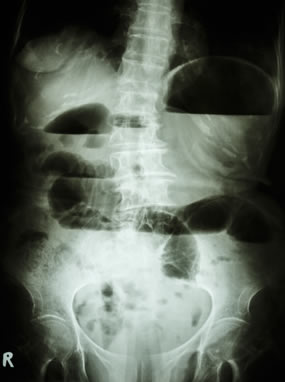

Οι απλές ακτινογραφίες κοιλίας αποτελούν την πιο σημαντική διαγνωστική δοκιμασία στον ειλεό. Πρέπει να γίνονται σε όρθια και σε ύπτια θέση. Αναδεικνύονται διατεταμένες έλικες λεπτού εντέρου (ημισεληνοειδείς διαυγάσεις) σε διάταξη κλίμακας στην ύπτια ακτινογραφία και υδραερικά επίπεδα, τα οποία είναι εμφανή στην απεικόνιση σε όρθια θέση.

Ακτινογραφία σε ύπτια θέση

Αυτά τα ευρήματα μπορεί να είναι ελάχιστα ή και απόντα στην πρώϊμη φάση της απόφραξης, στην εγγύς απόφραξη, την απόφραξη «κλειστής έλικας», ιδιαίτερα σε ισχαιμική περίσφιξη της τελευταίας, και σε περιπτώσεις που οι έλικες είναι γεμάτες με πολύ εντερικό υγρό και περιέχουν λίγο αέρα. Σε απόφραξη πέραν του 24ωρου, ο αέρας και τα κόπρανα έχουν κενωθεί από το παχύ έντερο, και αυτό φαίνεται στην απλή ακτινογραφία. Στην πρώϊμη φάση ωστόσο, αλλά και στις περιπτώσεις που η απόφραξη είναι μερική και ο ειλεός ατελής, κάποια ποσότητα αέρα ανευρίσκεται στο παχύ έντερο, και αυτό αποτελεί ένα από τα στοιχεία που διαχωρίζουν τον πλήρη από τον ατελή ειλεό.